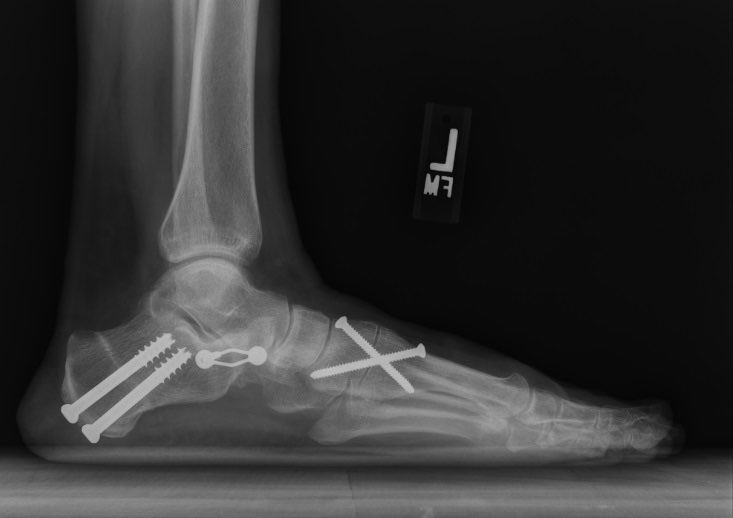

📍عند فشل العلاج التحفظي في تحسين آلام المريض، يتم اللجوء إلى الحل الجراحي 🔪، و الذي قد يشمل:

- إطالة الأوتار أو نقلها من مكان لأخر.

- قص و تعديل العظام.

- تثبيت مفاصل القدم في حالات متقدمة.